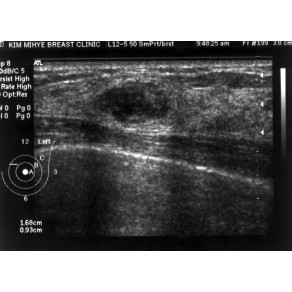

모양이 예뻐도 조금 의심스러운 종양은 조직검사가 좋습니다.

31세 여성이 만져지는 종괴를 주로소 내원하셨습니다.초음파검사를 하니 1.7cm의 경계가 비교적 …